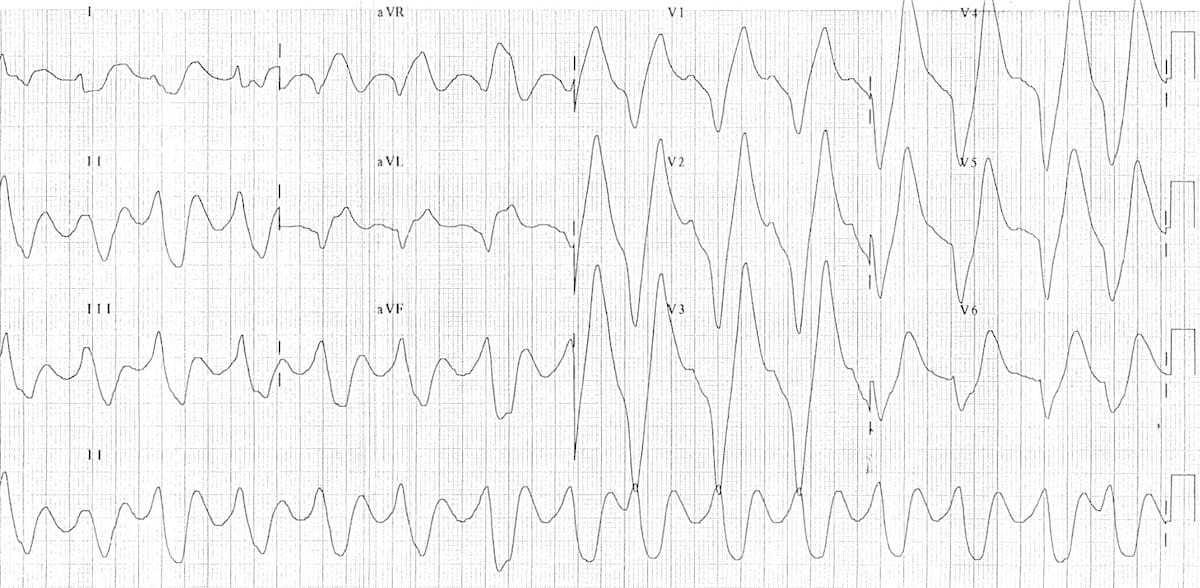

At a glance, the QRS in LVH has very high voltages, often overlapping across leads.

This is an ECG of LVH. Very deep S waves can be seen in V1-V3, with very tall R waves in V4-V6.

© Life in the Fast Lane. Licensed under CC BY-NC 4.0